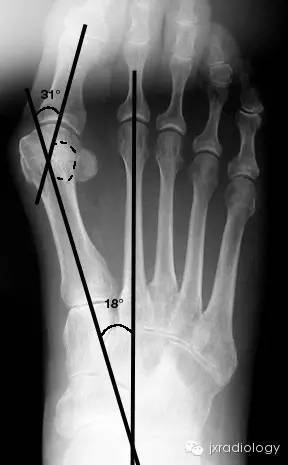

△ 常用测量角

常用测量角:

1、跖间角 (Intermetatarsal Angle, IMA) value币,第1、2跖骨纵轴延长线之夹角,正常6°~11°,正常 < 9°;

2、踇外翻角(Hallux Valgus Angle,HVA;又称 Hallux abductus angle,HAA)第1跖骨纵轴线与第1趾近节趾骨纵轴线之夹角,正常 < 20°value币。

踇外翻分度:

根据跖间角 (IMA)踇外翻角(HAA)的大小将其分为:

轻度(HAA:15°~30°;IMA≤13°);

中度(HAA:30°~40°;IMA:13°~16°);

重度(HAA≥40°;IMA≥16°)value币。